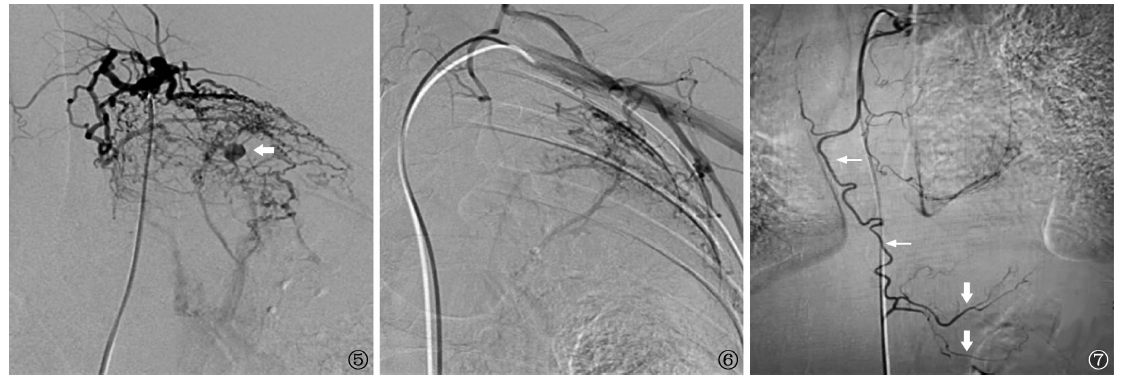

图5~7

图5

、6 为CT血管造影见左侧支气管动脉、左甲状颈干、左胸外侧动脉主干增粗、迂曲,远段分支增多、紊乱,可见大量纤细密集的病理性血管;肺动脉分支早期显影,形成支气管动脉-肺动脉瘘;左上肺野可见一假性动脉瘤(

箭示);

图7

为CT血管造影见左侧1支支气管动脉(细箭)异位起源于胃左动脉(粗箭)